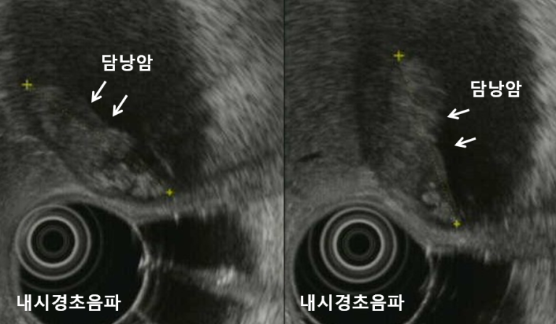

초음파 검사나 CT 촬영 등 영상의학적 검사를 통해 담낭에 이상이 관찰되면 담낭암을 의심합니다. 다른 암과 달리 담낭암은 조직 검사가 어려운 경우가 많아, 영상검사에서 암이 의심될 경우 조직 검사를 생략하고 수술 치료로 바로 진행하는 경우가 많습니다. 또한 담관 전이 여부를 확인하기 위해 내시경적 역행성 췌담관 조영술(ERCP)을 시행할 수 있습니다.